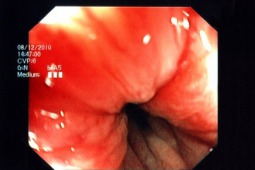

Na łamach Colorectal Disease opublikowano wyniki prospektywnego, randomizowanego badania, w którym dokonano oceny przydatności napoju Coca-Cola Zero® jako środka używanego do rozpuszczania polietylenoglikolu (PEG) w ramach przygotowania do kolonoskopii. Pytanie postawione w badaniu jest istotne, dlatego że właściwe przygotowanie jelita do badania kolonoskopowego jest warunkiem jego wiarygodności diagnostycznej. Dlatego też czynione są starania, aby schemat oczyszczania jelita był jak najprostszy i najmniej kłopotliwy dla pacjenta, ponieważ wtedy zwiększa się stopień przestrzegania zasad przygotowania do badania (tzw. compliance).

Autorzy przeprowadzili badanie, w którym uczestniczyło 209 zdrowych osób (114 mężczyzn, 95 kobiet), którzy poddawani byli planowym badaniom kolonoskopowym. W sposób randomizowany przydzielano chorych do dwóch podgrup, które przygotowywały się nieco odmiennie do kolonoskopii: w jednej z podgrup rozpuszczano PEG w Coca-Coli Zero® (n=100), a w drugiej w sposób klasyczny – czyli w wodzie (n=109). Dane na temat m.in. akceptowalności, działań niepożądanych były raportowane za pomocą specjalnie skonstruowanego kwestionariusza.

Akceptowalność (w tym smak roztworu) sposobu oczyszczania jelita była istotnie większa w podgrupie, stosującej Coca Colę. Także istotnie większy odsetek (55% vs. 43%) badanych zadeklarowało, że w przypadku kolejnej kolonoskopii wybrałoby sposób przygotowania z użyciem Coca Coli. Wykazano także, że średni czas potrzebny do spożycia wymaganej ilości środka przeczyszczającego był istotnie krótszy w tej podgrupie badanych. Co ciekawe, także jakość przygotowania jelita grubego do kolonoskopii była istotnie lepsza w podgrupie, stosującej Coca Colę. Nie było natomiast różnic w odsetku odnotowanych działań niepożądanych, a także odsetku wykrytych polipów jelita grubego. Nie wykazano także, aby użycie Coca Coli do rozpuszczenia PEG wiązało się z ryzykiem wystąpienia zaburzeń elektrolitowych u pacjentów.

Podsumowując, autorzy wykazali, że Coca Cola Zero® może być alternatywnym środkiem, stosowanym do rozpuszczenia PEG w ramach przygotowania jelita do kolonoskopii. Zastosowanie tego napoju może zwiększać akceptowalność sposobu oczyszczania jelita i, co za tym idzie, poprawić jakość tego przygotowania.